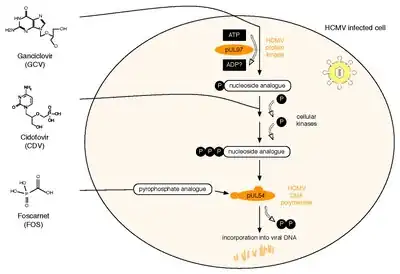

Ganciclovir (Cytovene) treatment is used for people with depressed immunity who have either sight-related or life-threatening illnesses. Valganciclovir (Valcyte) is an antiviral drug that is also effective and is given orally: it is a pro-drug that gets converted into ganciclovir in the body, but is much better absorbed orally than the latter. The therapeutic effectiveness is frequently compromised by the emergence of drug-resistant virus isolates. A variety of amino acid changes in the UL97 protein kinase and the viral DNA polymerase have been reported to cause drug resistance. Foscarnet or cidofovir are only given to people with CMV resistant to ganciclovir, because foscarnet has notable nephrotoxicity, resulting in increased or decreased Ca2+ or PO43−, and decreased Mg2+ levels.[72][73]

All three currently licensed anti-HCMV drugs target the viral DNA polymerase, pUL54. Ganciclovir (GCV) acts as nucleoside analogue. Its antiviral activity requires phosphorylation by the HCMV protein kinase, pUL97.[76] The second drug, Cidofovir (CDV), is a nucleotide analogue, which is already phosphorylated and thus active. Finally, Foscarnet (FOS) has a different mode of action. It directly inhibits polymerase function by blocking the pyrophosphate binding site of pUL54 (note: investigational drug letermovir acts through a mechanism that involves viral terminase).[77] Two HCMV proteins are implicated in antiviral resistance against these three drugs: pUL97 and pUL54. Specific mutations in pUL97 can cause reduced phosphorylation activity of this viral protein kinase. Thus, fewer monophosphorylated – and thus active – GCV can be synthesized,[78] leading to antiviral resistance against GCV. About 90% of all GCV resistances are caused by such mutations in UL97.[79] Mutations in pUL54 may have different effects leading to antiviral drug resistance: A. They can lead to decreased affinity to antiviral compounds. This resistance mechanism concerns GCV, CDV and FOS and may lead to multidrug resistance.[80] B. Some mutations in pUL54 can increase the polymerase's exonuclease activity. This causes enhanced recognition of incorporated GCV and CDV. As a result, these dNTP analogues are excised more efficiently. Major risk factors for HCMV drug resistance are the residual capacity of the host's immune system to control viral replication and the overall amount and duration of viral replication.[81] HCMV antiviral drug resistance can be detected by phenotypic or by genotypic drug resistance testing. Phenotypic resistance testing involves cultivation of the virus in cell culture and testing its susceptibility using different antiviral drug concentrations in order to determine EC50 values. In contrast, genotypic resistance testing means the detection of resistance associated mutations in UL97 and UL54 by sequencing. Genotypic resistance testing is becoming the method of choice because it is faster, but requires previous phenotypic characterisation of each newly found mutation. This can be performed via a web-based search tool that links a person's HCMV sequence to a database containing all published UL97 and UL54 mutations and corresponding antiviral drug susceptibility phenotypes.[82]